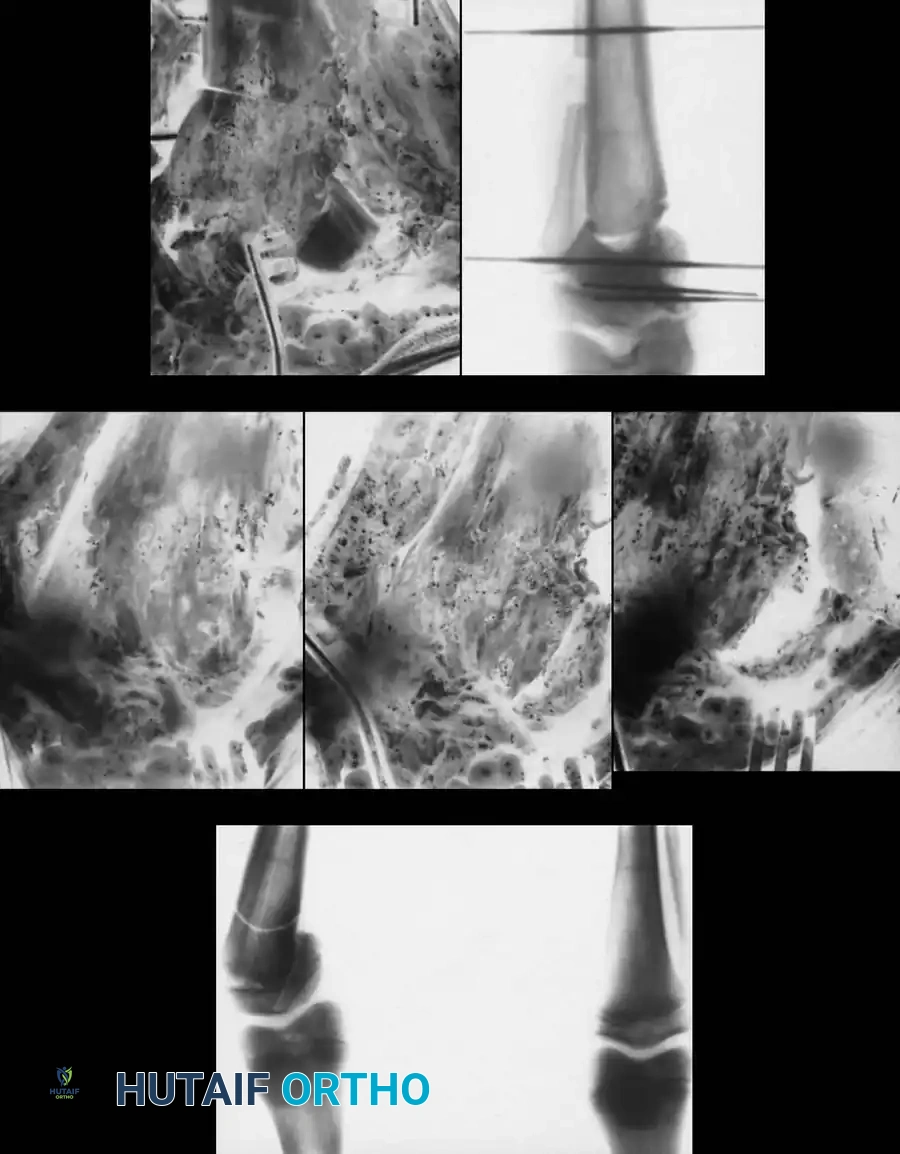

Step-by-Step Surgical Technique (Proximal Tibial Osteotomy)

- Positioning and Preparation: The patient is positioned supine on a radiolucent table. A tourniquet is applied to the proximal thigh. Fluoroscopy must be available to visualize the mechanical axis from the center of the femoral head to the center of the ankle mortise.

- Fibular Osteotomy: A fibular osteotomy is mandatory to allow tibial correction. This is typically performed in the middle third of the fibula to avoid the common peroneal nerve proximally and the distal tibiofibular syndesmosis distally. An oblique cut is made to allow sliding.

- Tibial Exposure: A transverse or longitudinal incision is made over the proximal tibia, distal to the tibial tubercle to avoid the apophysis. The anterior compartment musculature is elevated laterally.

- Osteotomy Execution: Guide pins are placed under fluoroscopic guidance to define the osteotomy plane. The cut is made distal to the tibial tubercle to ensure the extensor mechanism remains attached to the proximal fragment.

- Deformity Correction: The distal fragment is translated laterally, angulated into valgus, and externally rotated to correct the multiplanar deformity.

- Fixation: Fixation depends on surgeon preference and patient age. Options include crossed Kirschner wires incorporated into a long-leg cast, rigid internal fixation (plates and screws), or external fixation (Ilizarov or Taylor Spatial Frame), which allows for gradual postoperative correction.

1. Intraepiphyseal Osteotomy: To elevate the depressed medial tibial plateau and reconstruct the horizontal joint line.

2. Metaphyseal Valgus Osteotomy: To correct the diaphyseal varus angulation.

Schoenecker et al. reported successful elevation of the medial tibial plateau in patients aged 10 to 13 years with average preoperative varus deformities of 25 degrees. The procedure involves an osteotomy through the epiphysis, elevating the medial plateau to match the lateral plateau, and supporting the elevation with structural bone graft.

Surgical Warning: Intraepiphyseal osteotomies carry a high risk of intra-articular fracture, avascular necrosis of the elevated fragment, and permanent physeal arrest. Meticulous fluoroscopic guidance and rigid fixation are absolute requirements.